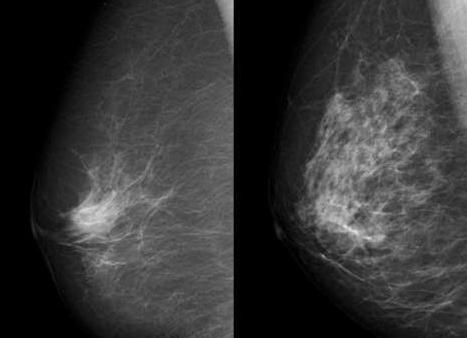

• Вторая стадия. Инфильтрирующая карцинома молочной железы 2 степени затрагивает подмышечные лимфоузлы, не дает отдаленных метастазов и характеризуется диаметром в пределах 2-5 см.

• Маммография. Применяется для скрининга образования у женщин в возрасте от 40 лет. Позволяет обнаружить опухолевые очаги, в том числе и безвредные. Для получения более точных данных в крупных диагностических центрах используется трехмерное исследование.

• Маммография. Это рентген груди, который дает возможность найти опухоли размером более 0,5 см и микрокальцинаты (характерный признак онкологии).